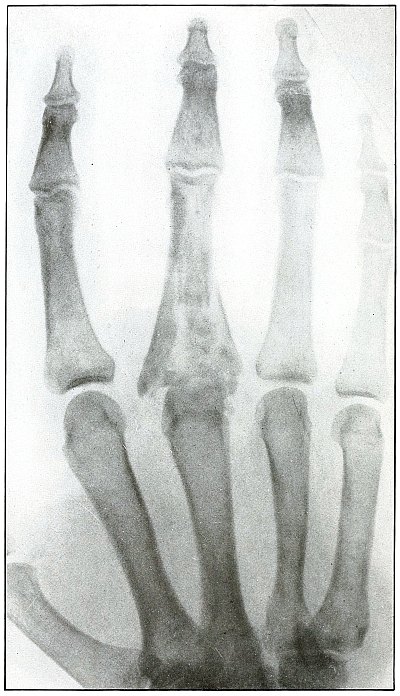

Plate 44.

[Pg 99]

Rifle—Plate 44.

UPPER EXTREMITY.

Gunshot Fracture of the Third Phalanx.

The course of the bullet was anteroposterior through the base of the

proximal phalanx of the middle finger, with a velocity of long range.

It practically punctured the bones and split off a few fragments

without displacement.

The wound of entrance would be much the same as the wound of exit,

with the latter, but a little larger.

Treatment is conservative.